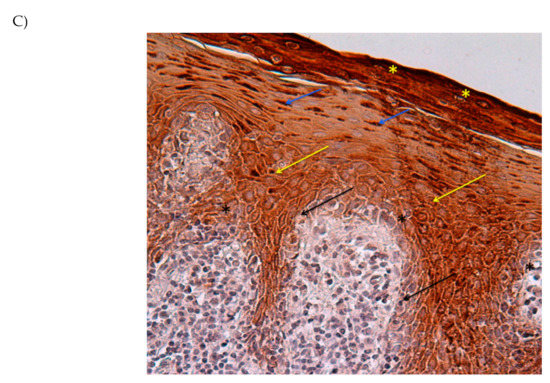

- In the peri-implantitis specimens, the epithelium is a well-defined tissue organized with compartments with a demarcation line between epidermis and dermis clearly evident.

- Beneath the epithelial layer, the dermis is not organized and shows the morphology of an inflamed tissue (ICT).

- The ICT is about of 60% of the connective tissue present in the underlying dermis

- The marginal portion of the ICT has large numbers of collagen fibers occurring together with several lymphocytes and plasma cells.

- Collagen fibers are parallel to the line of the epithelium and often free of the cell.

- Inflammatory cells mostly occupy the lesion and are formed by neutrophilic granulocytes;